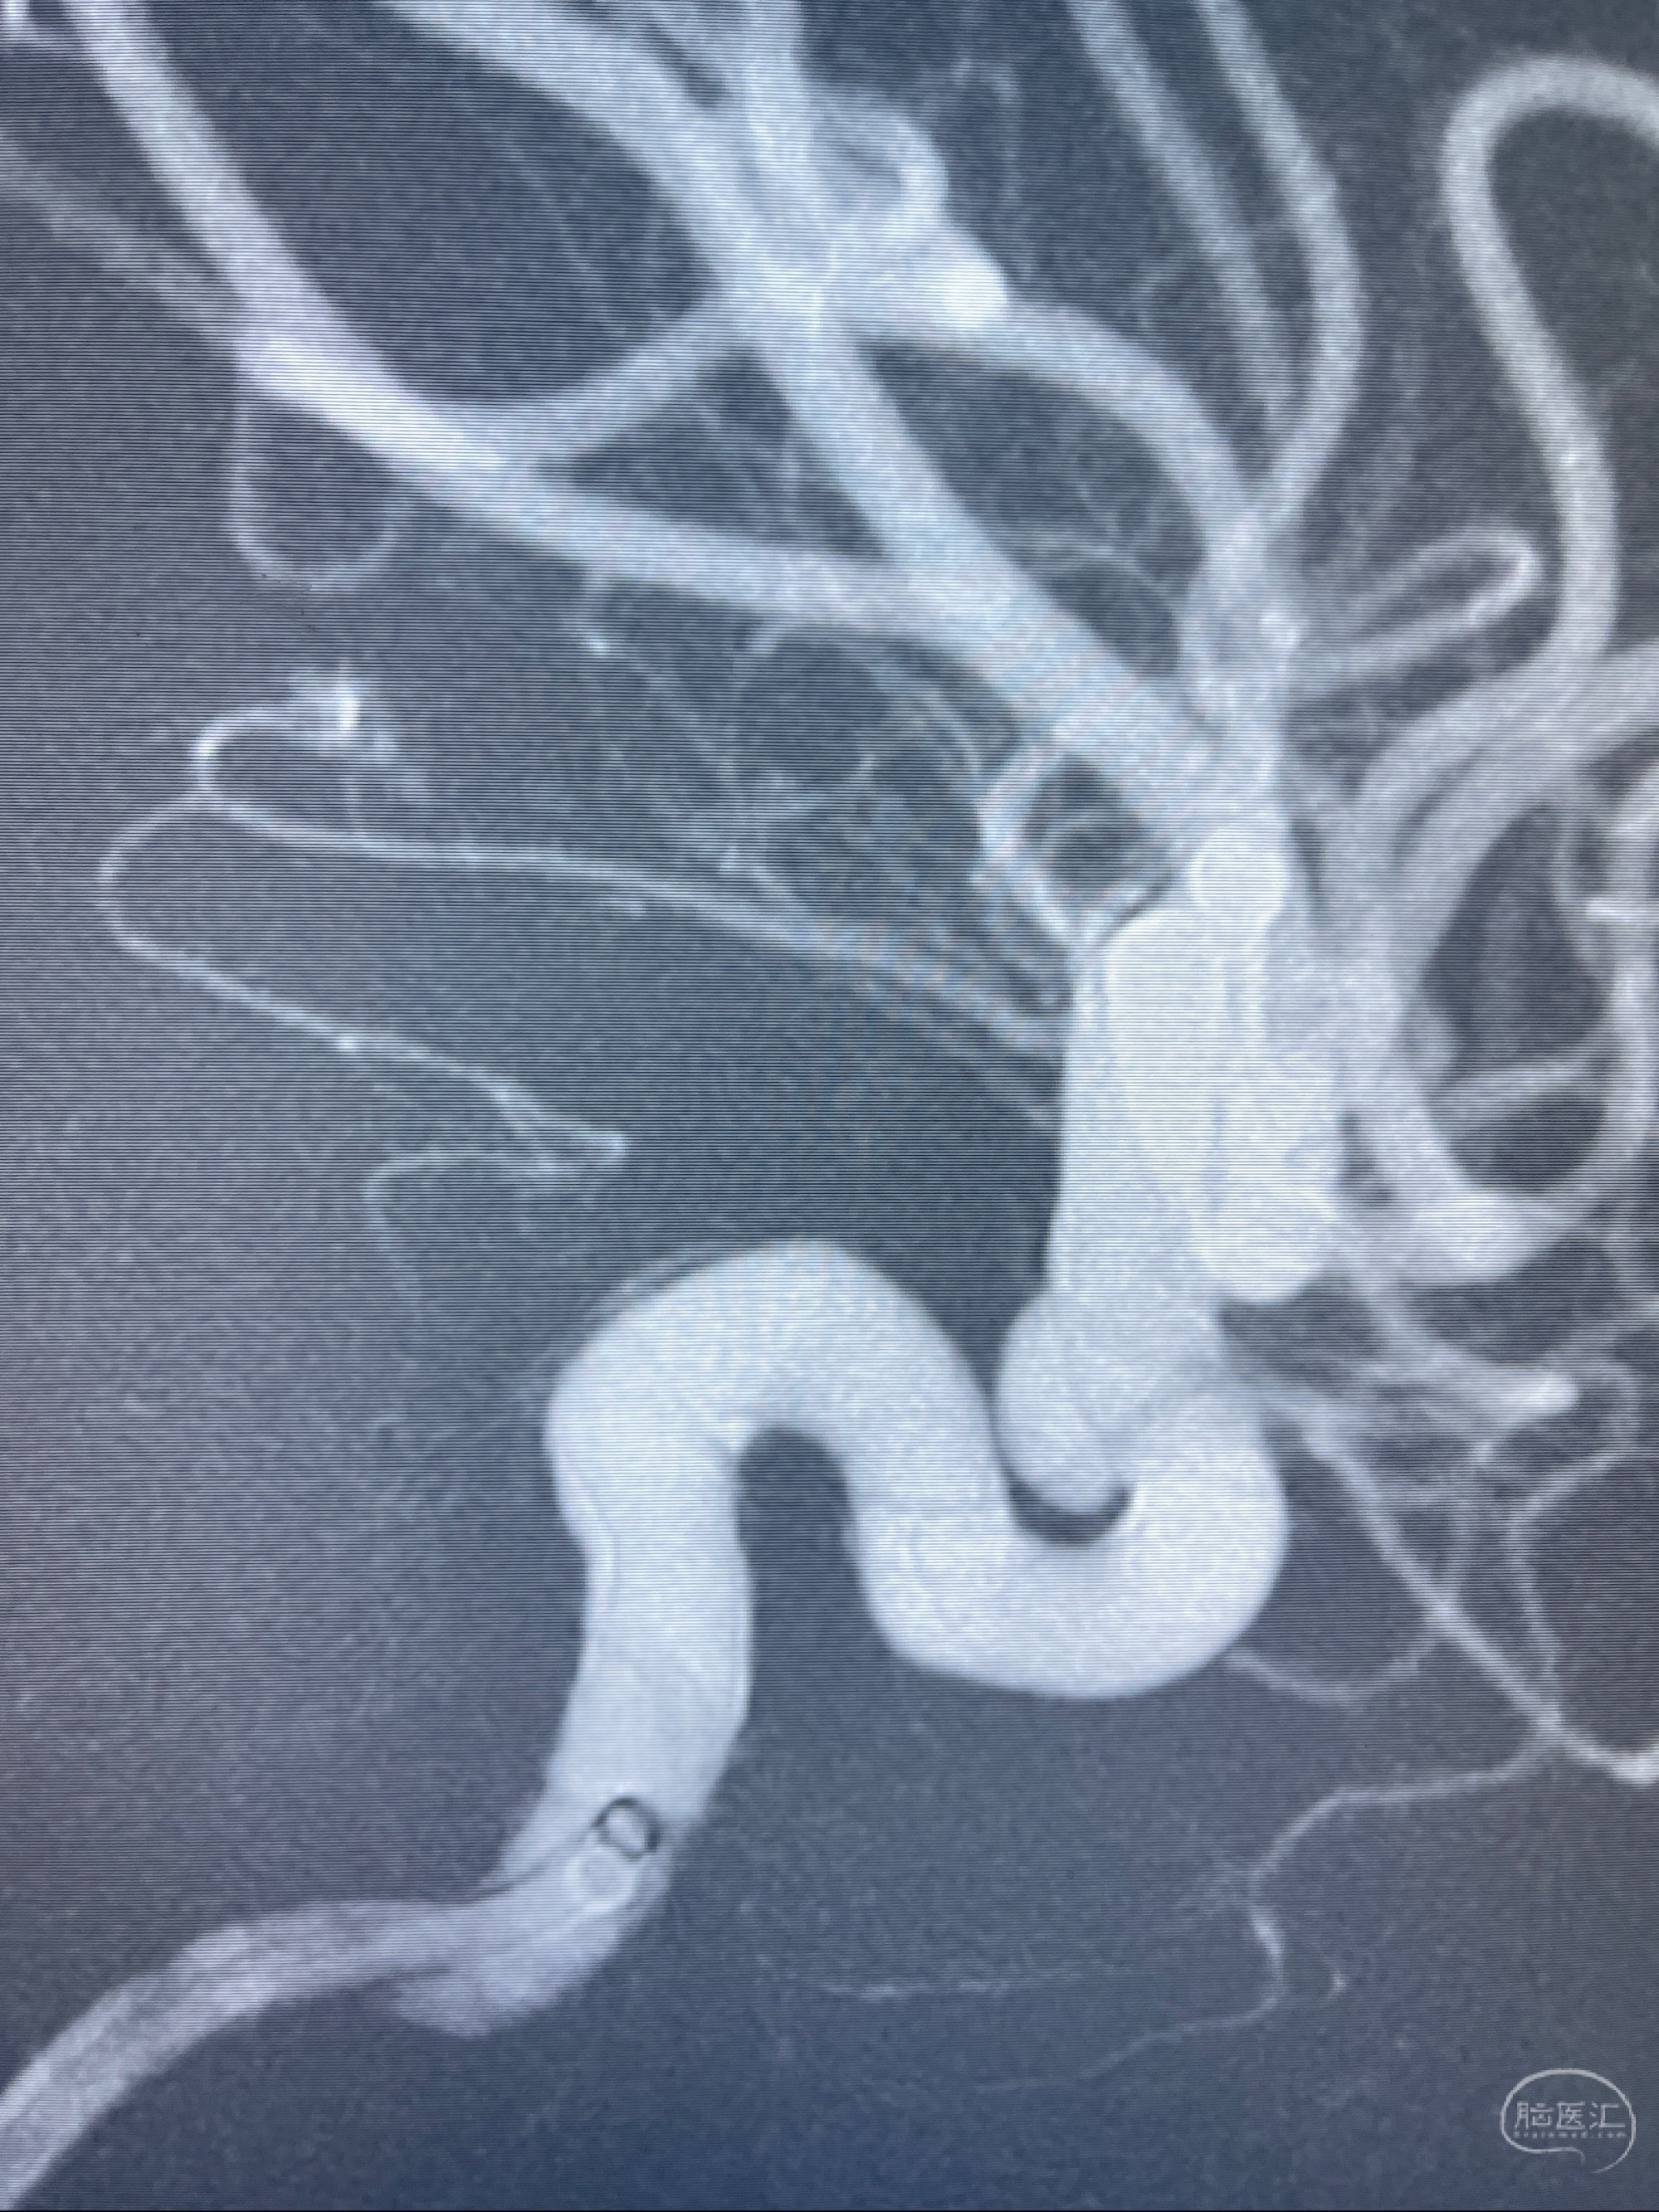

2023.07.25 泰州市人民医院查头颅CTA提示右侧C6段瘤样突起,建议DSA检查;

CTA示:右侧颈内动脉C6段见指向下方的突起,余左侧颈内动脉、双侧椎动脉、大脑前动脉、大脑中动脉、大脑后动脉及基底动脉走形正常,未见明显扩张及狭窄,局部未见明显瘤样扩张。

看原图,应该有两侧动脉瘤😅

2023-07-27全脑血管造影:双侧颈内动脉眼动脉段动脉瘤,右侧较大